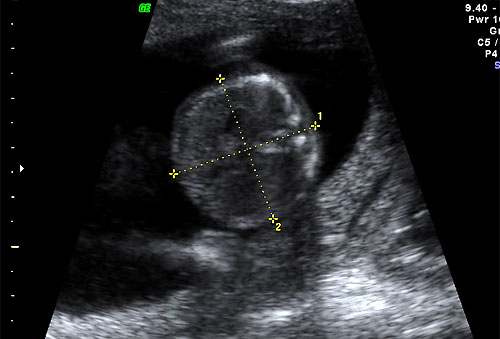

Normal BPD and HC at 16 weeks |

Normal 16 week OFD measurement |